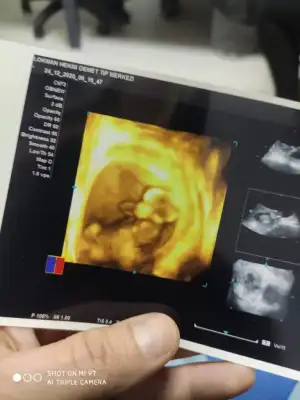

Erkek12 haftalık bana da bakabilir misiniz![]()

Diğer taraftaki konumda yazdim erkek gibi sanki tekrar USG paylasin12 haftalık bana da bakabilir misiniz![]()

12 haftalık USG bu çok teşekkür ederimDiğer taraftaki konumda yazdim erkek gibi sanki tekrar USG paylasin

Başka USG paylaşın12 haftalık USG bu çok teşekkür ederim![]()

8 haftalık budaBaşka USG paylaşın![]()